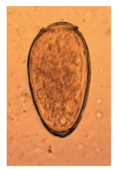

Ascaris lumbricoides (large intestinal roundworm) fert

knowt flashcard image